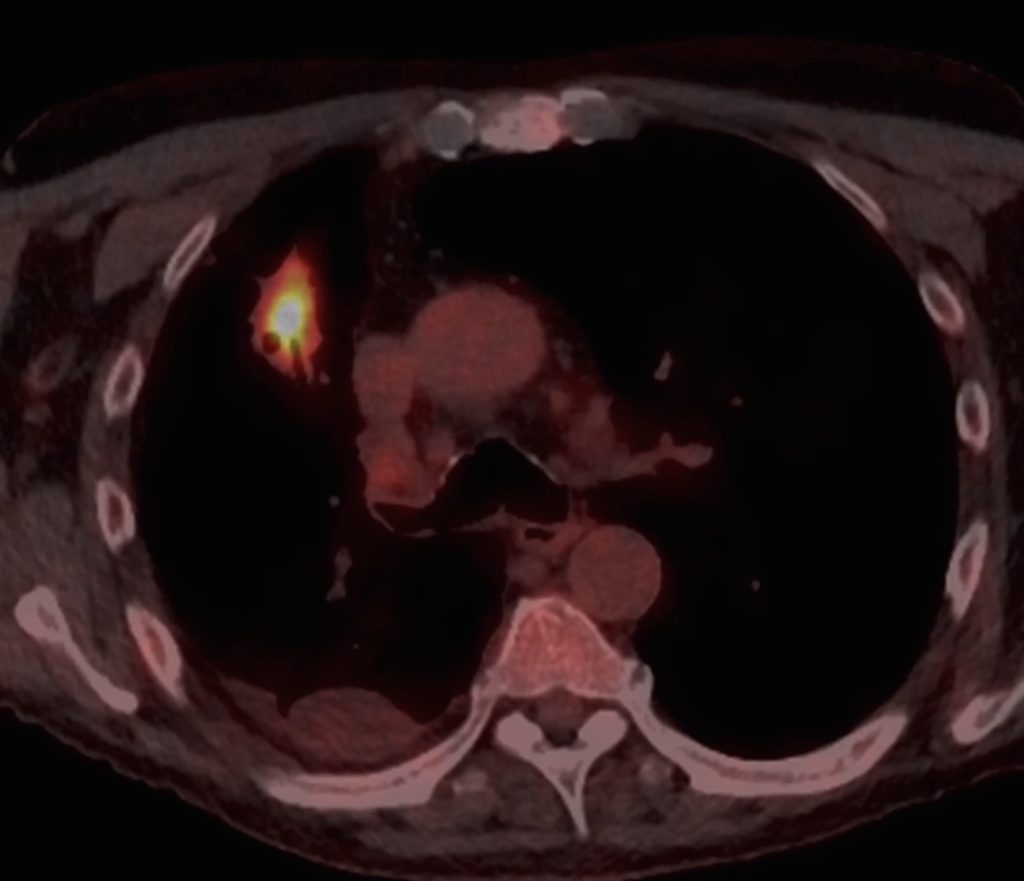

PET-CT review

Since the patient’s inflammatory markers were elevated, but the appearance was concerning, a PET-CT scan was performed.

Both opacities were FDG-avid meaning malignancy couldn’t be ruled out.

On this image we can see FDG avidity within the right upper lobe lesion on PET-CT.